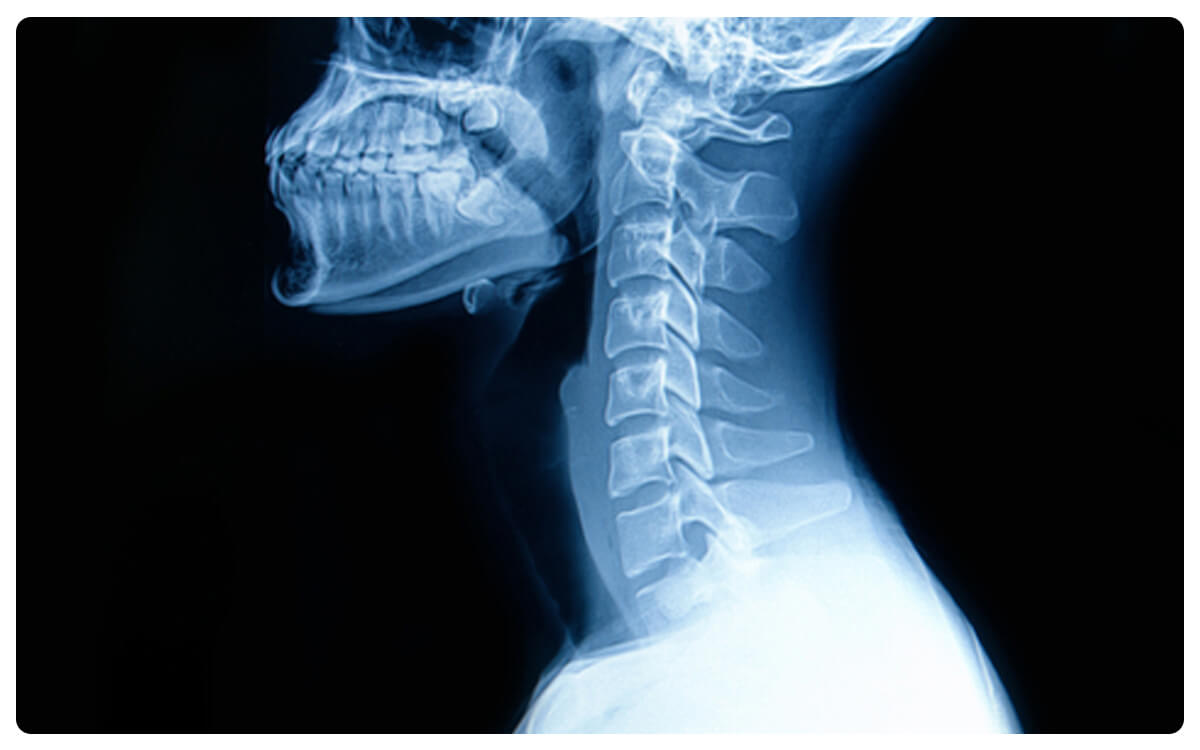

La Radiografía de Columna Cervical en proyecciones Anteroposterior (AP) y Lateral se presenta como una herramienta esencial en la radiología diagnóstica, brindando una visión completa y detallada de la anatomía y posibles afecciones de la región cervical. A través de la emisión controlada de radiación, estas técnicas no invasivas proporcionan imágenes bidimensionales que permiten la evaluación de la alineación, estructura ósea y posibles problemas en la columna cervical desde ángulos frontales y laterales.

Las Radiografías de Columna cervical AP y lateral desempeñan un papel crucial en la detección y diagnóstico de lesiones, desgaste, malformaciones y otras patologías que afectan la columna vertebral en esta región, ofreciendo información esencial para la toma de decisiones clínicas informadas y el manejo adecuado de las afecciones cervicales.